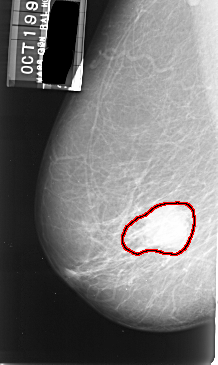

A_1006_1.LEFT_CC

LEFT_CC LINES 5416 PIXELS_PER_LINE 2866 BITS_PER_PIXEL 16 RESOLUTION 42 OVERLAY

FILE: A_1006_1.LEFT_CC.OVERLAY

TOTAL_ABNORMALITIES 1

ABNORMALITY 1

LESION_TYPE MASS SHAPE IRREGULAR MARGINS ILL_DEFINED

ASSESSMENT 4

SUBTLETY 5

PATHOLOGY MALIGNANT

TOTAL_OUTLINES 1

BOUNDARY